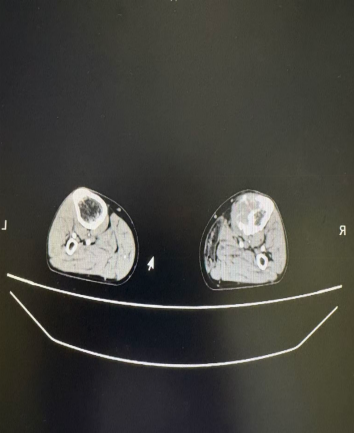

案例四:贾先生,61岁,右侧胫骨继发性恶性肿瘤(发病时无法站立行走)。2025年10月25日,在CT引导下右侧胫骨转移性肿瘤粒子植入术,术后可独立行走,生活质量显著提升。

术前                                                                            术后                                                                              现可独立行走